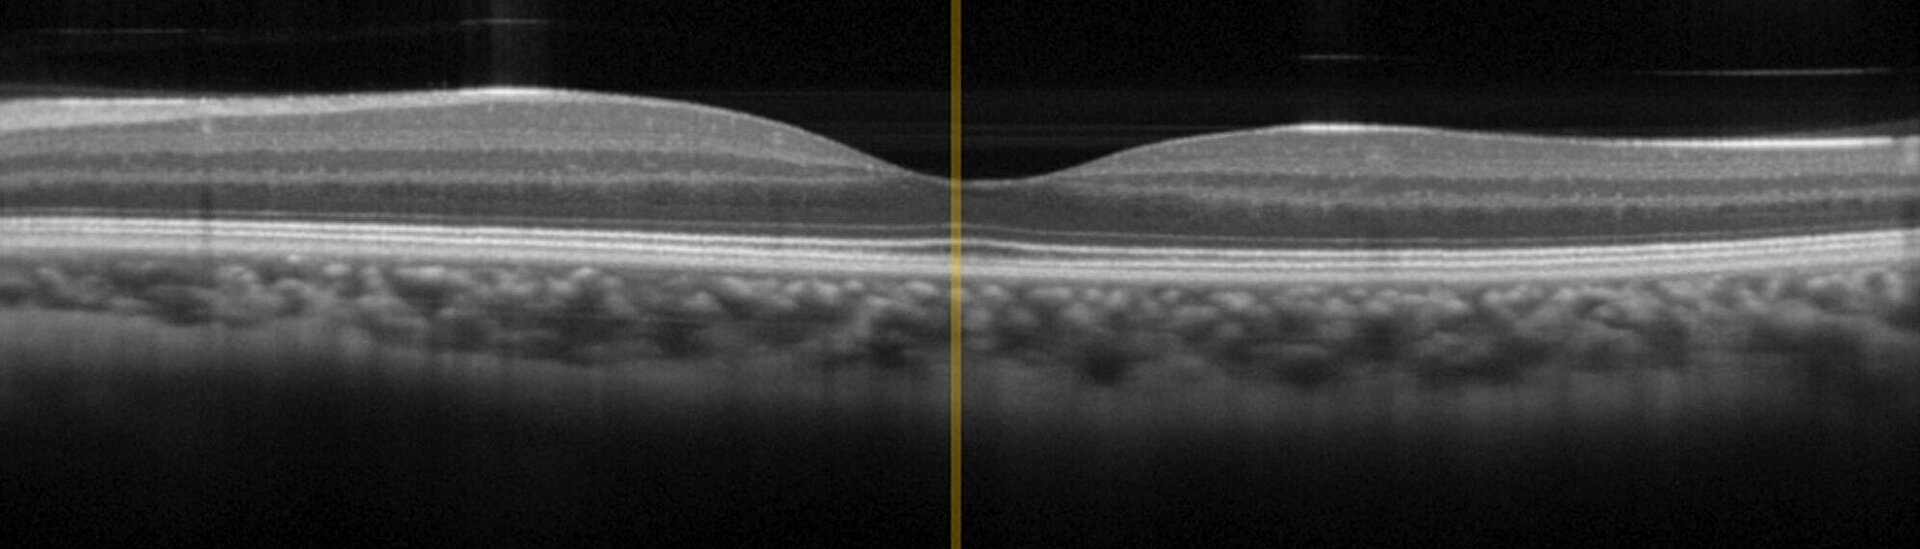

OCTは、組織への最適な透過性を実現するための、0.8μmから1.4μmの波長域の広帯域赤外光による干渉イメージング技術です。OCTはすでに眼科学において 「ゴールドスタンダード」 に達していますが、近年では皮膚がんの診断など、皮膚病学への応用も広がっています。従来の侵襲型の診断法と比較し、OCTはより迅速に結果をもたらし、患者への副作用やストレスを軽減します。